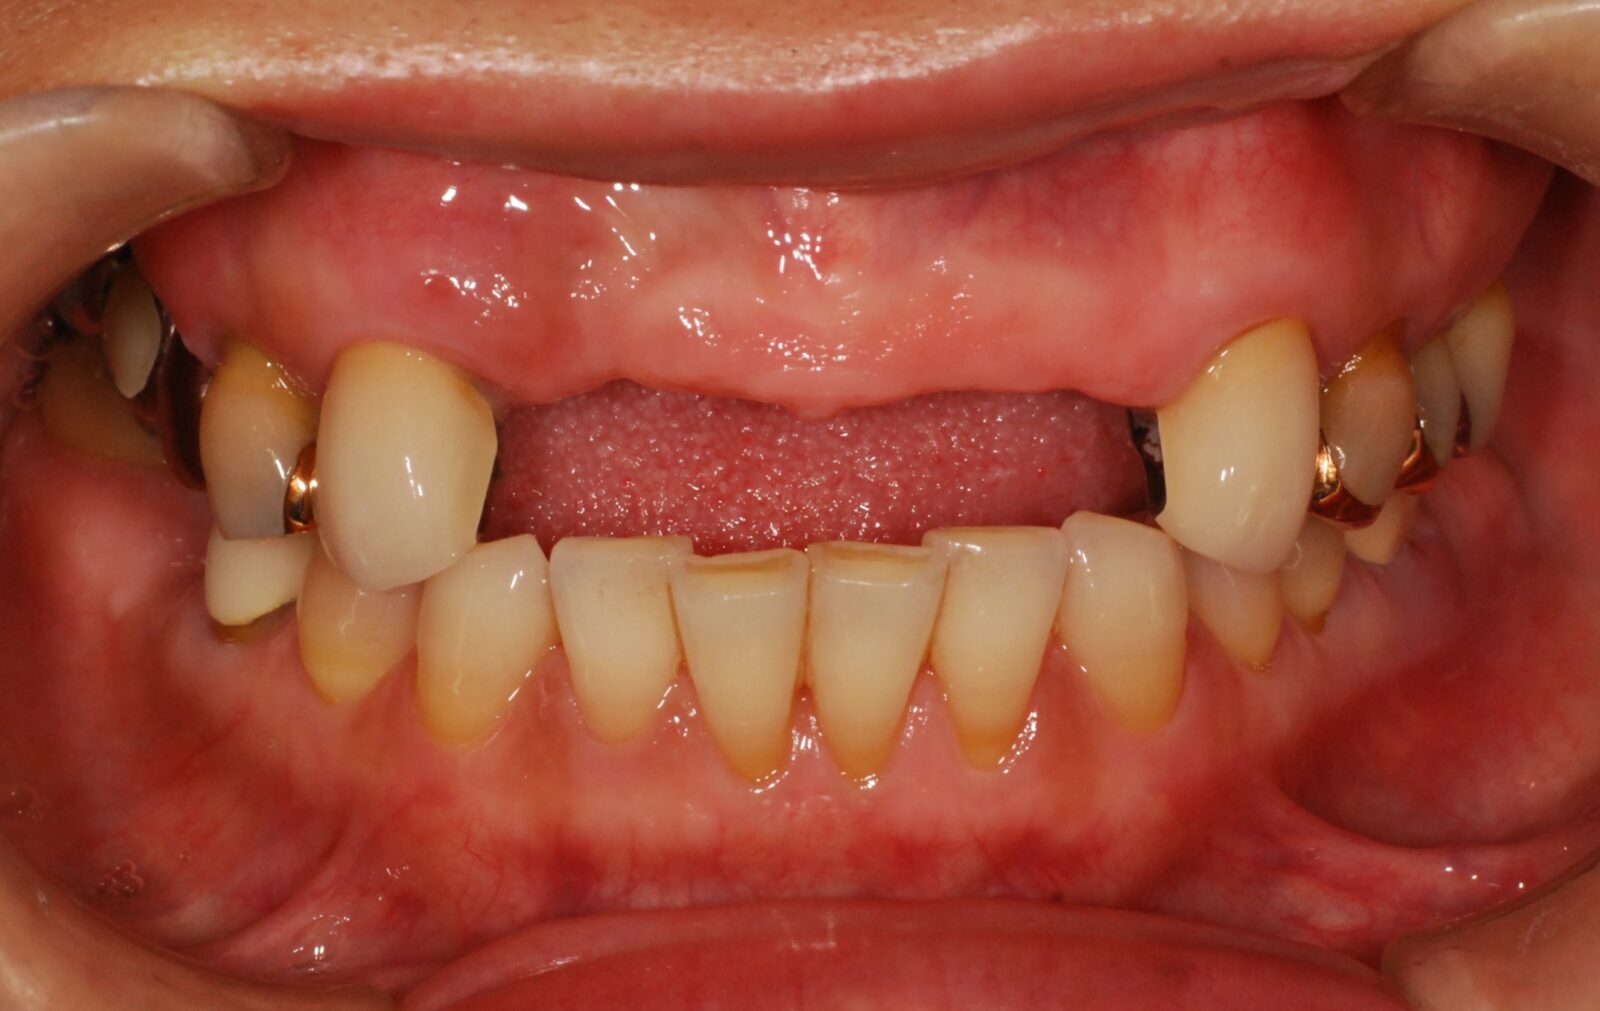

金属のバネが見えるのが嫌な方、もっとぴったりと密着した入れ歯を望まれる方にお勧めしているのが、右のように、金属のバネがない入れ歯「ノンクラスプ義歯」です。

金属バネ部分を、歯茎に近い色の樹脂で作ることで目立ちにくくしています。

当院では、「スマイルデンチャー」というノンクラスプ義歯を扱っています。

価格は約220,000円(税込)。ノンクラスプデンチャーを用いた症例。リスクとしては、過度の衝撃で割れることがあります。